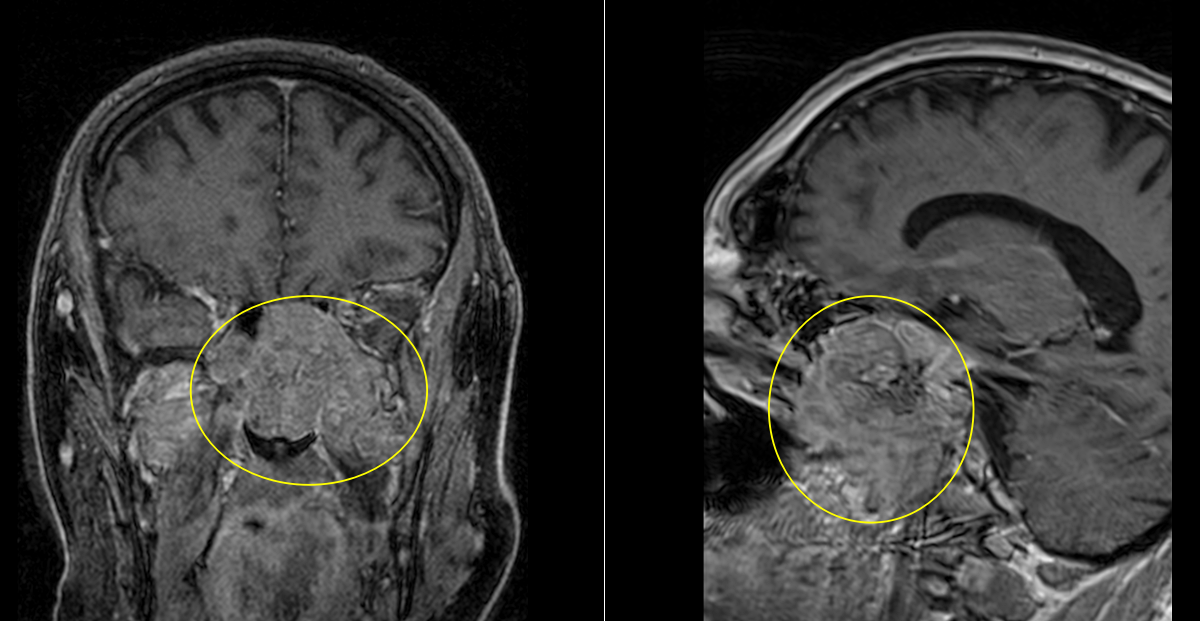

A. Imagistică:

- CT cranian cu reconstrucție 3D: evidențiază detalii osoase.

- RMN cerebral cu contrast: evaluează extensia intracraniană, vasele și nervii implicați.

B. Condrosarcomul

Tumoră malignă ce derivă din țesut cartilaginos.

Frecvent localizat la baza craniului (clivus, sfenoid).

Simptome: cefalee, diplopie, afectarea nervilor cranieni.

Creștere lentă, dar invazivă.

Tratament: excizie chirurgicală completă + radioterapie postoperatorie.

C. Cordomul

Tumoră rară, malignă, ce derivă din resturi embrionare ale notocordului.

Apare frecvent la nivelul clivusului (baza craniului).

Se dezvoltă lent, dar are potențial invaziv.

Simptome: durere, pareze oculomotorii, tulburări de deglutiție.

Tratament: rezecție chirurgicală maximală + radioterapie stereotactică – protonoterapia sau radioterapia cu ioni de carbon.